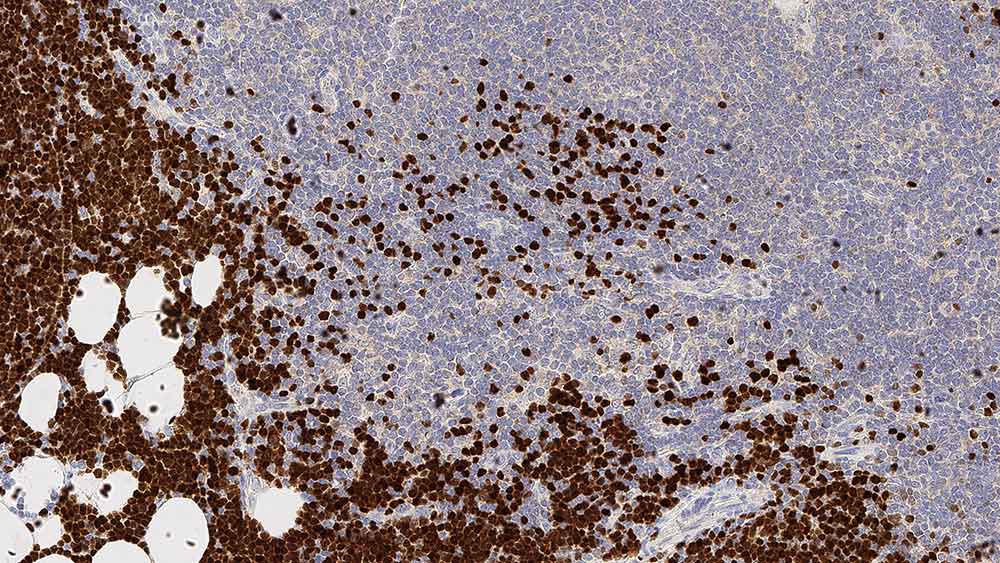

Hodgkin's lymphoma: immunohistochemical staining with Fascin: clone IM20

Human fascin is a 55 to 58 kD actin-bundling protein, whose actin binding ability is regulated by phosphorylation. In normal tissues the detection of fascin is reported to be predominantly restricted to dendritic cells, and in the thymus has been observed only in medullary dendritic cells. In reactive nodes, interdigitating reticulum cells of T cell zones, cells in subcapsular areas, and cells of the reticular network express fascin. Variable expression is seen in follicular dendritic cells and endothelial cells. Lymphoid cells, myeloid cells and plasma cells do not express fascin; however, in cases of Hodgkin's disease, including nodular sclerosis, mixed cellularity lymphocyte depletion and unclassified cases, most or all Reed Sternberg cells are reported to be positive for fascin. Fascin expression may be induced by Epstein-Barr virus (EBV) infection of B cells with the possibility that viral induction of fascin in lymphoid or other cell types must also be considered in EBV-positive cases.